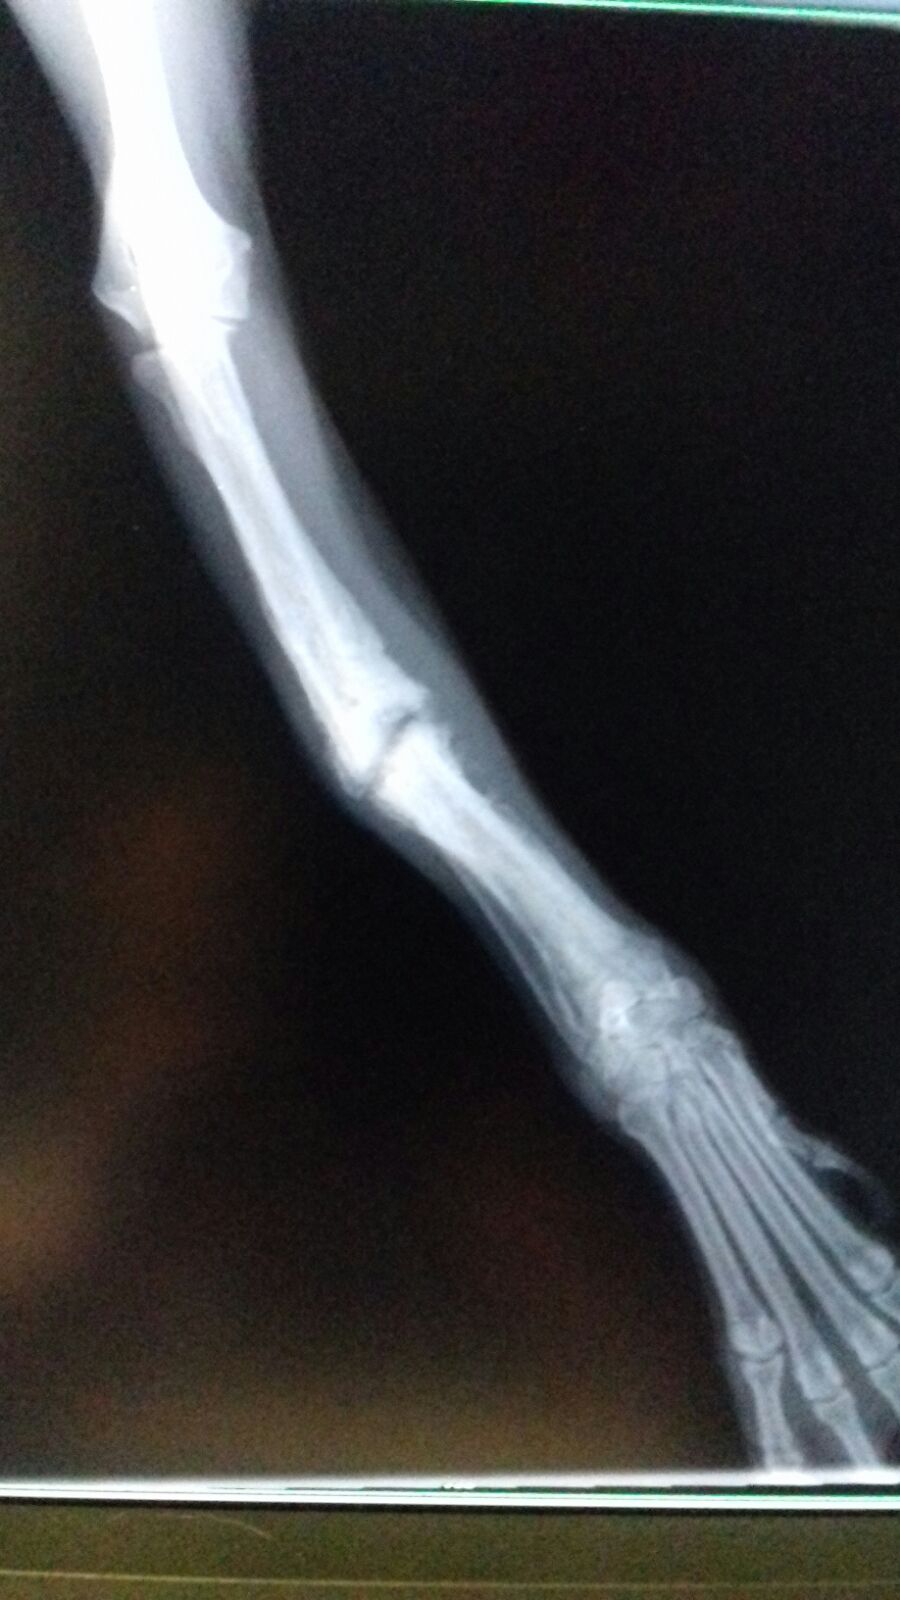

Im Rahmen der Kastration wurde auch Ricardas rechtes Vorderbein geröntgt. Die italienischen Tierärzte möchten nicht mehr daran rühren, aber wir lassen die Röntgenaufnahmen noch in Deutschland von einem Spezialisten für Orthopädie begutachten und hoffen, dass der lieben Hündin doch noch geholfen werden kann!

Ricardas gebrochenes Bein wird am 19.04. durch eine Operation stabilisiert. Damit stehen ihre Chancen sehr gut, dass sie ihr Bein bald wieder vollständig und schmerzfrei belasten kann!